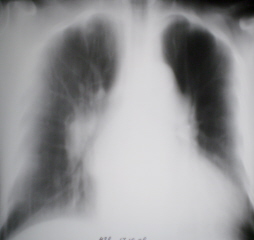

Иллюстрации 3, 4. Фрагменты рентгенограммы правого лёгкого и участка правого корня с увеличением.

Иллюстрации 5, 6. Рентгенограмма в правой боковой проекции и фрагмент с увеличением.